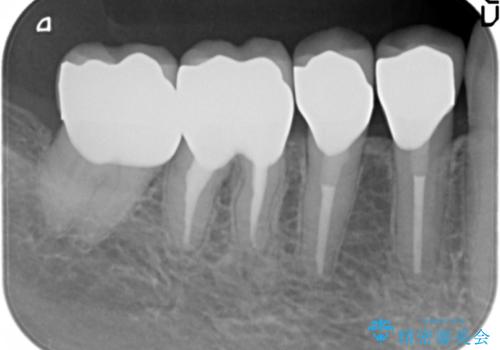

大臼歯 再根管治療

せっかく銀歯を白くしても後々根管治療が必要になり、また壊して再治療を行うことを避けたいとの事でしたので、再根管治療から行っていきます。

ただ銀歯を白くするのではなく長期的な予後には歯の内部、根管治療の成功が必要不可欠です。

- 根管治療により痛みや腫れがひかない事や、術後に痛みや腫れが生じる事、治療によるファイル破折やパーフォレーションなどの偶発症、術後の歯根破折を生じる可能性もあります